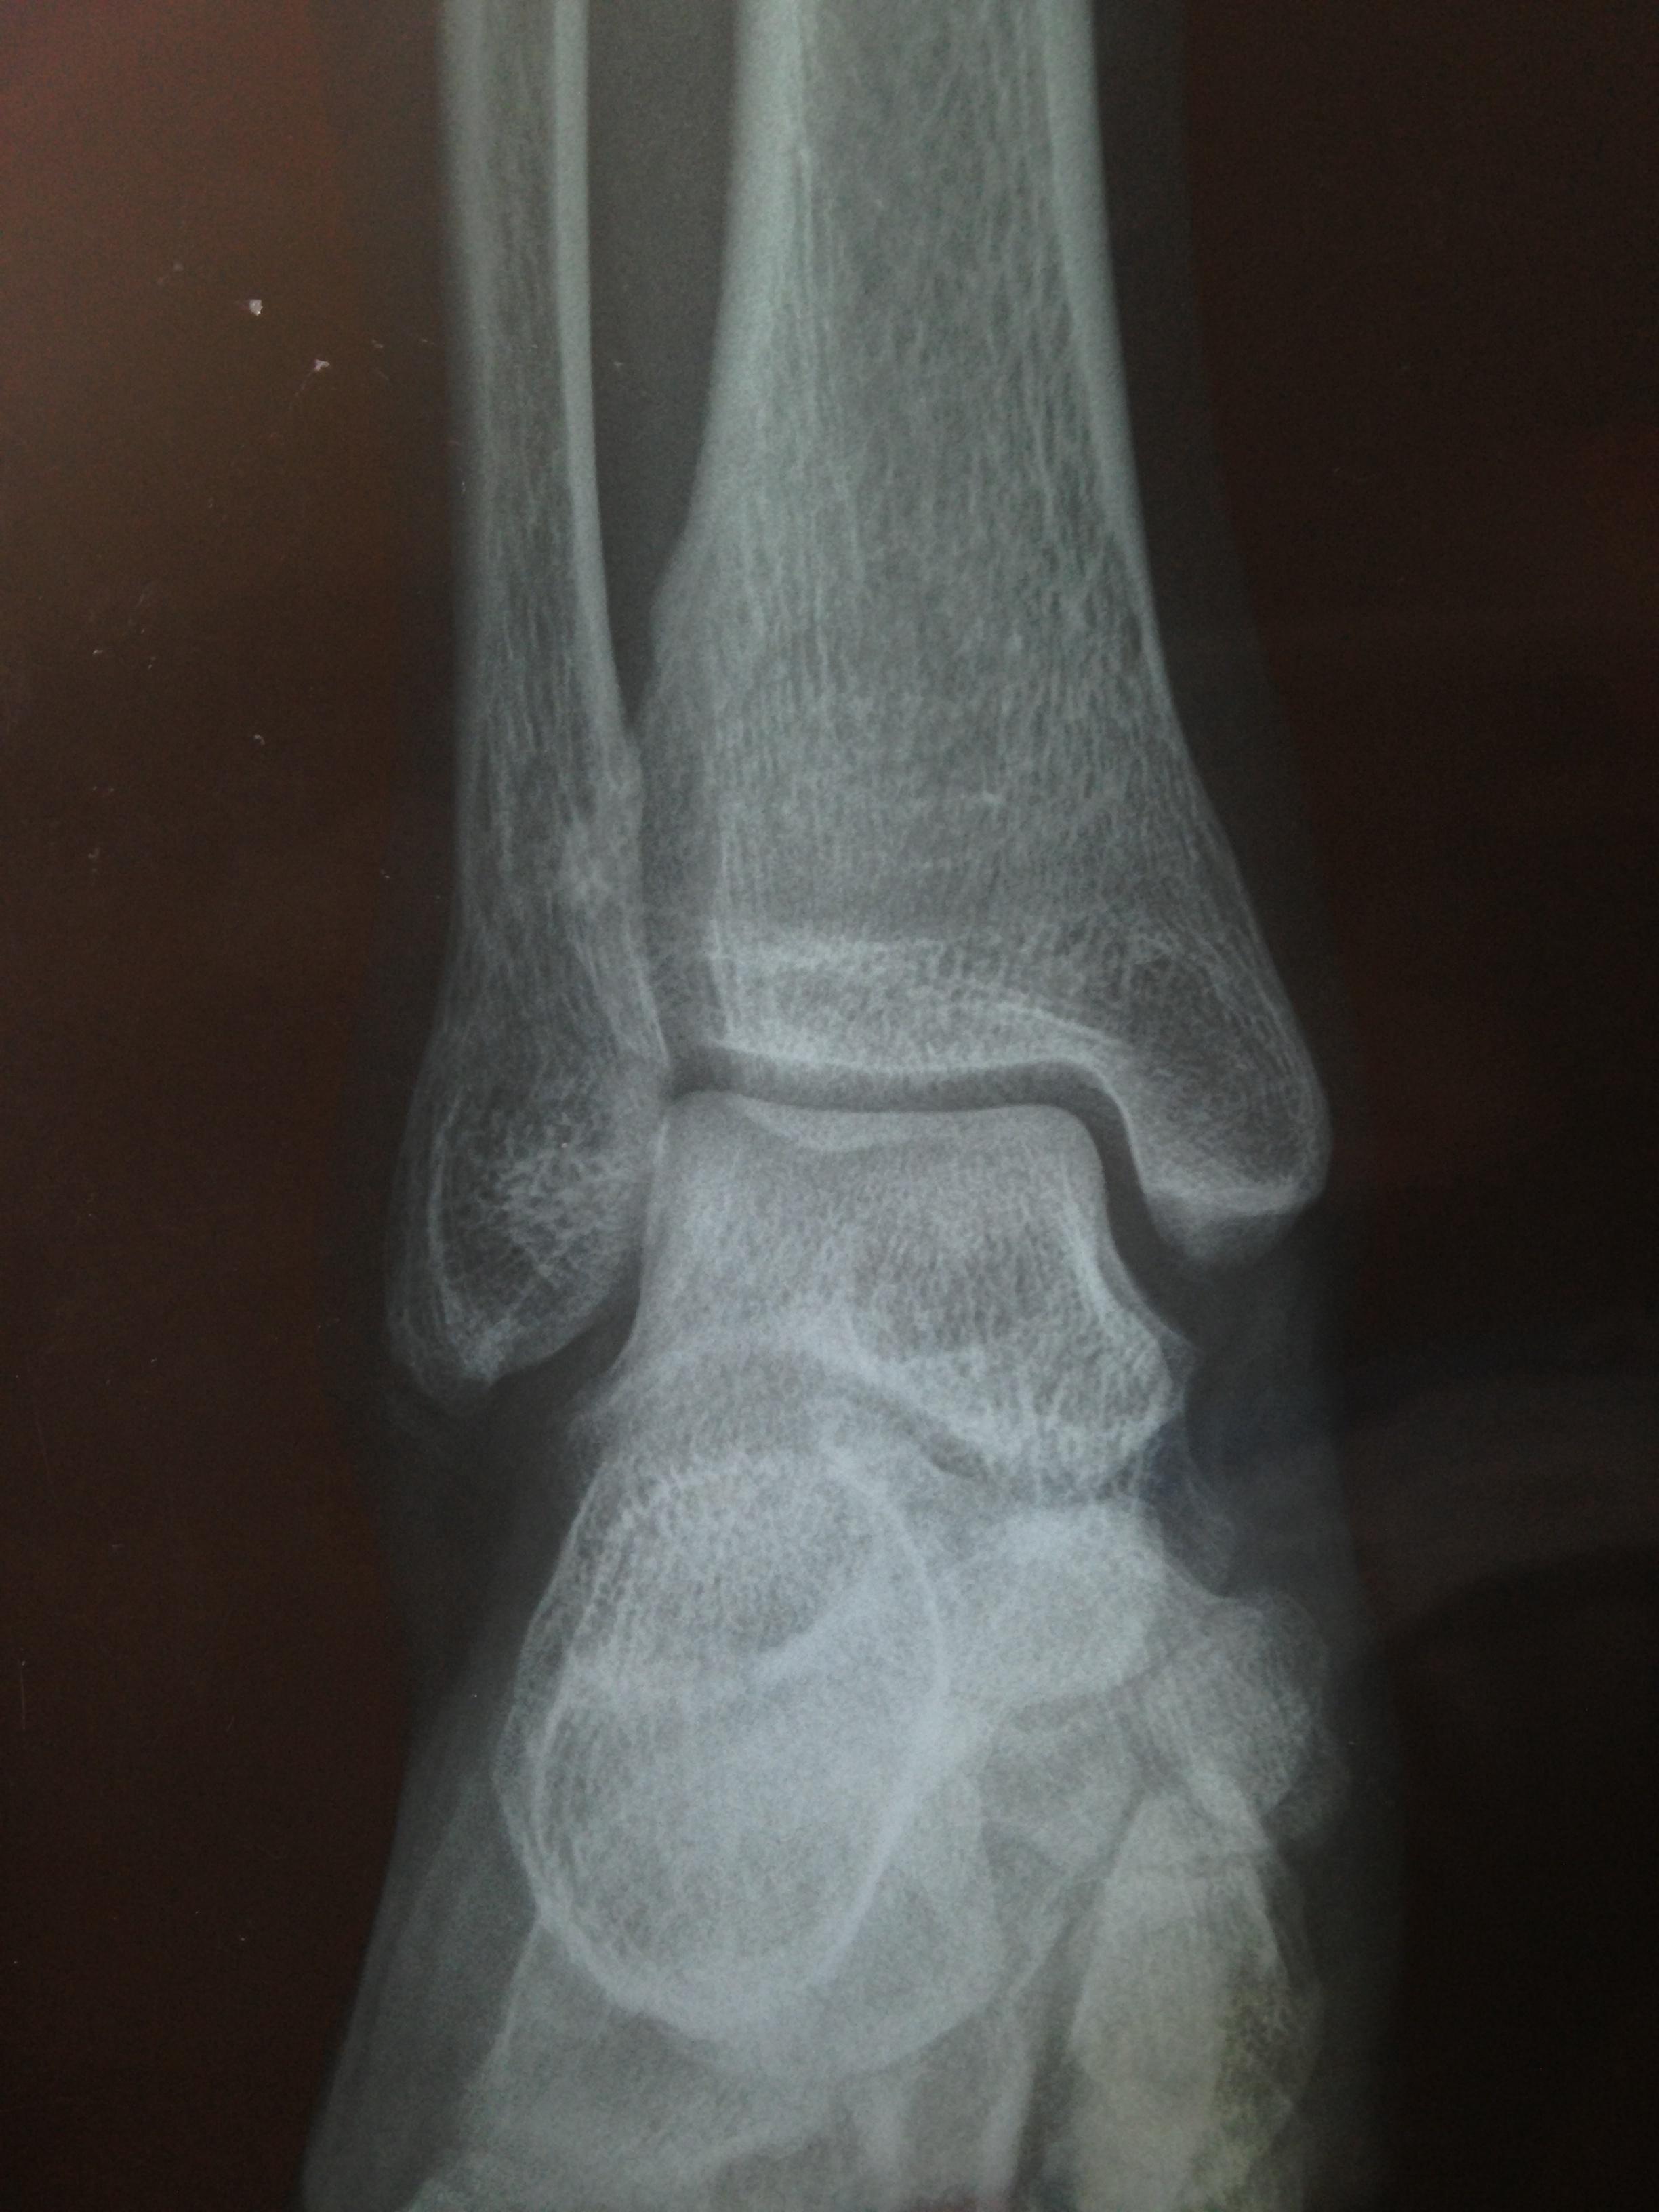

距骨重叠三角形骨片影

撕脱的骨片在侧位哪里?